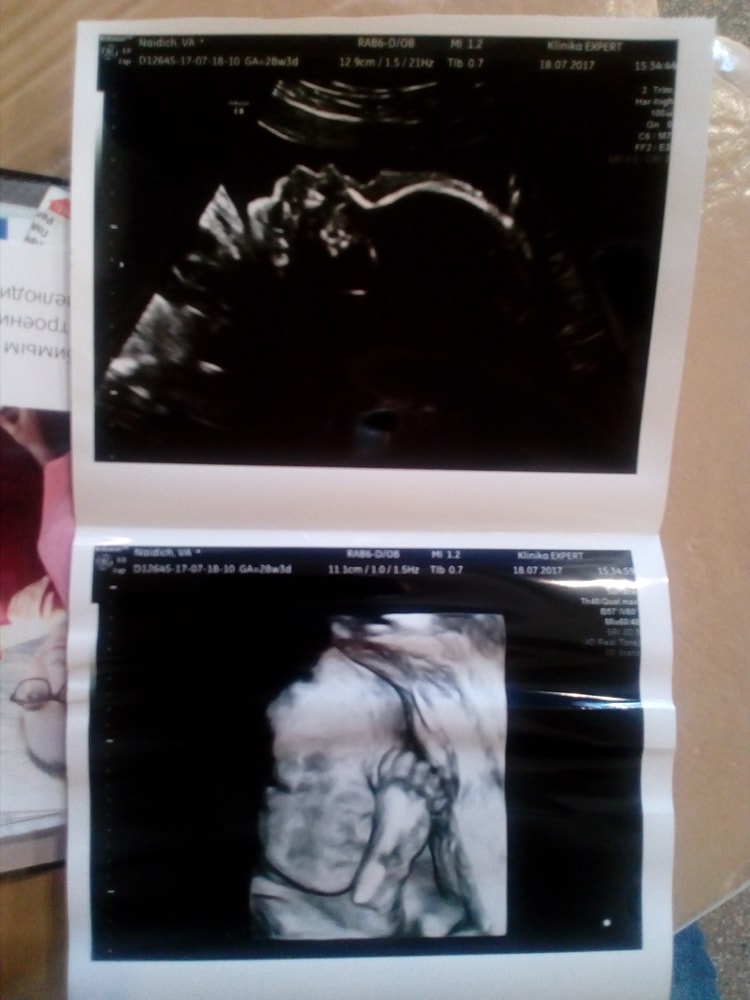

Изображение Вот кстати нашла фотку со старшим)) ему 8 лет исполняется сегодня, пересматривала фотки, ностальгировала и нашла его фотку 3Д. Тоже 28-29 недель, 8 лет назад делали

Изображение вот 28-29